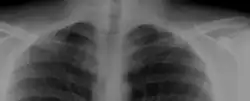

Most cases of cervical ribs are not clinically relevant and do not have symptoms;[12][13] cervical ribs are generally discovered incidentally, most often during x-rays and CT scans.[8][9][11] However, they vary widely in size and shape,[8] and in rare cases, they may cause problems such as contributing to thoracic outlet syndrome,[12] because they press on the nerves.[12][14]

On imaging, cervical ribs can be distinguished because their transverse processes are directed inferolaterally, whereas those of the adjacent thoracic spine are directed anterolaterally.[16]